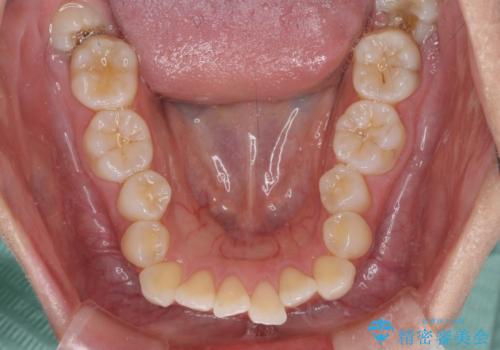

前歯のデコボコを解消 インビザラインの矯正治療

- 前歯のデコボコを治したいとのことで来院された患者様です。

上下顎ともに歯列全体の後方移動とIPR(歯と歯の間を削る)によってデコボコが解消するように設計し、インビザラインにより治療を行うこととしました。